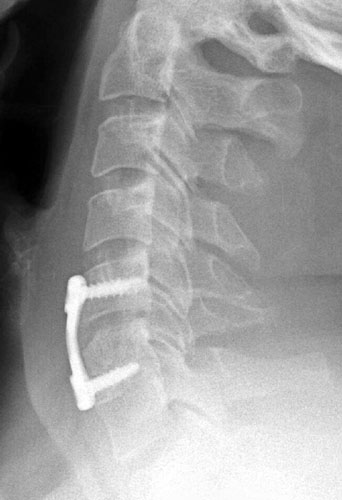

Lateral radiograph taken 3 months post-operatively for a routine survey. Careful examination of the positioning of the screws relative to each other one can note that on the prior film, the screws are parallel to each other. Now, the screws converge anteriorly slightly, consistent with graft collapse.